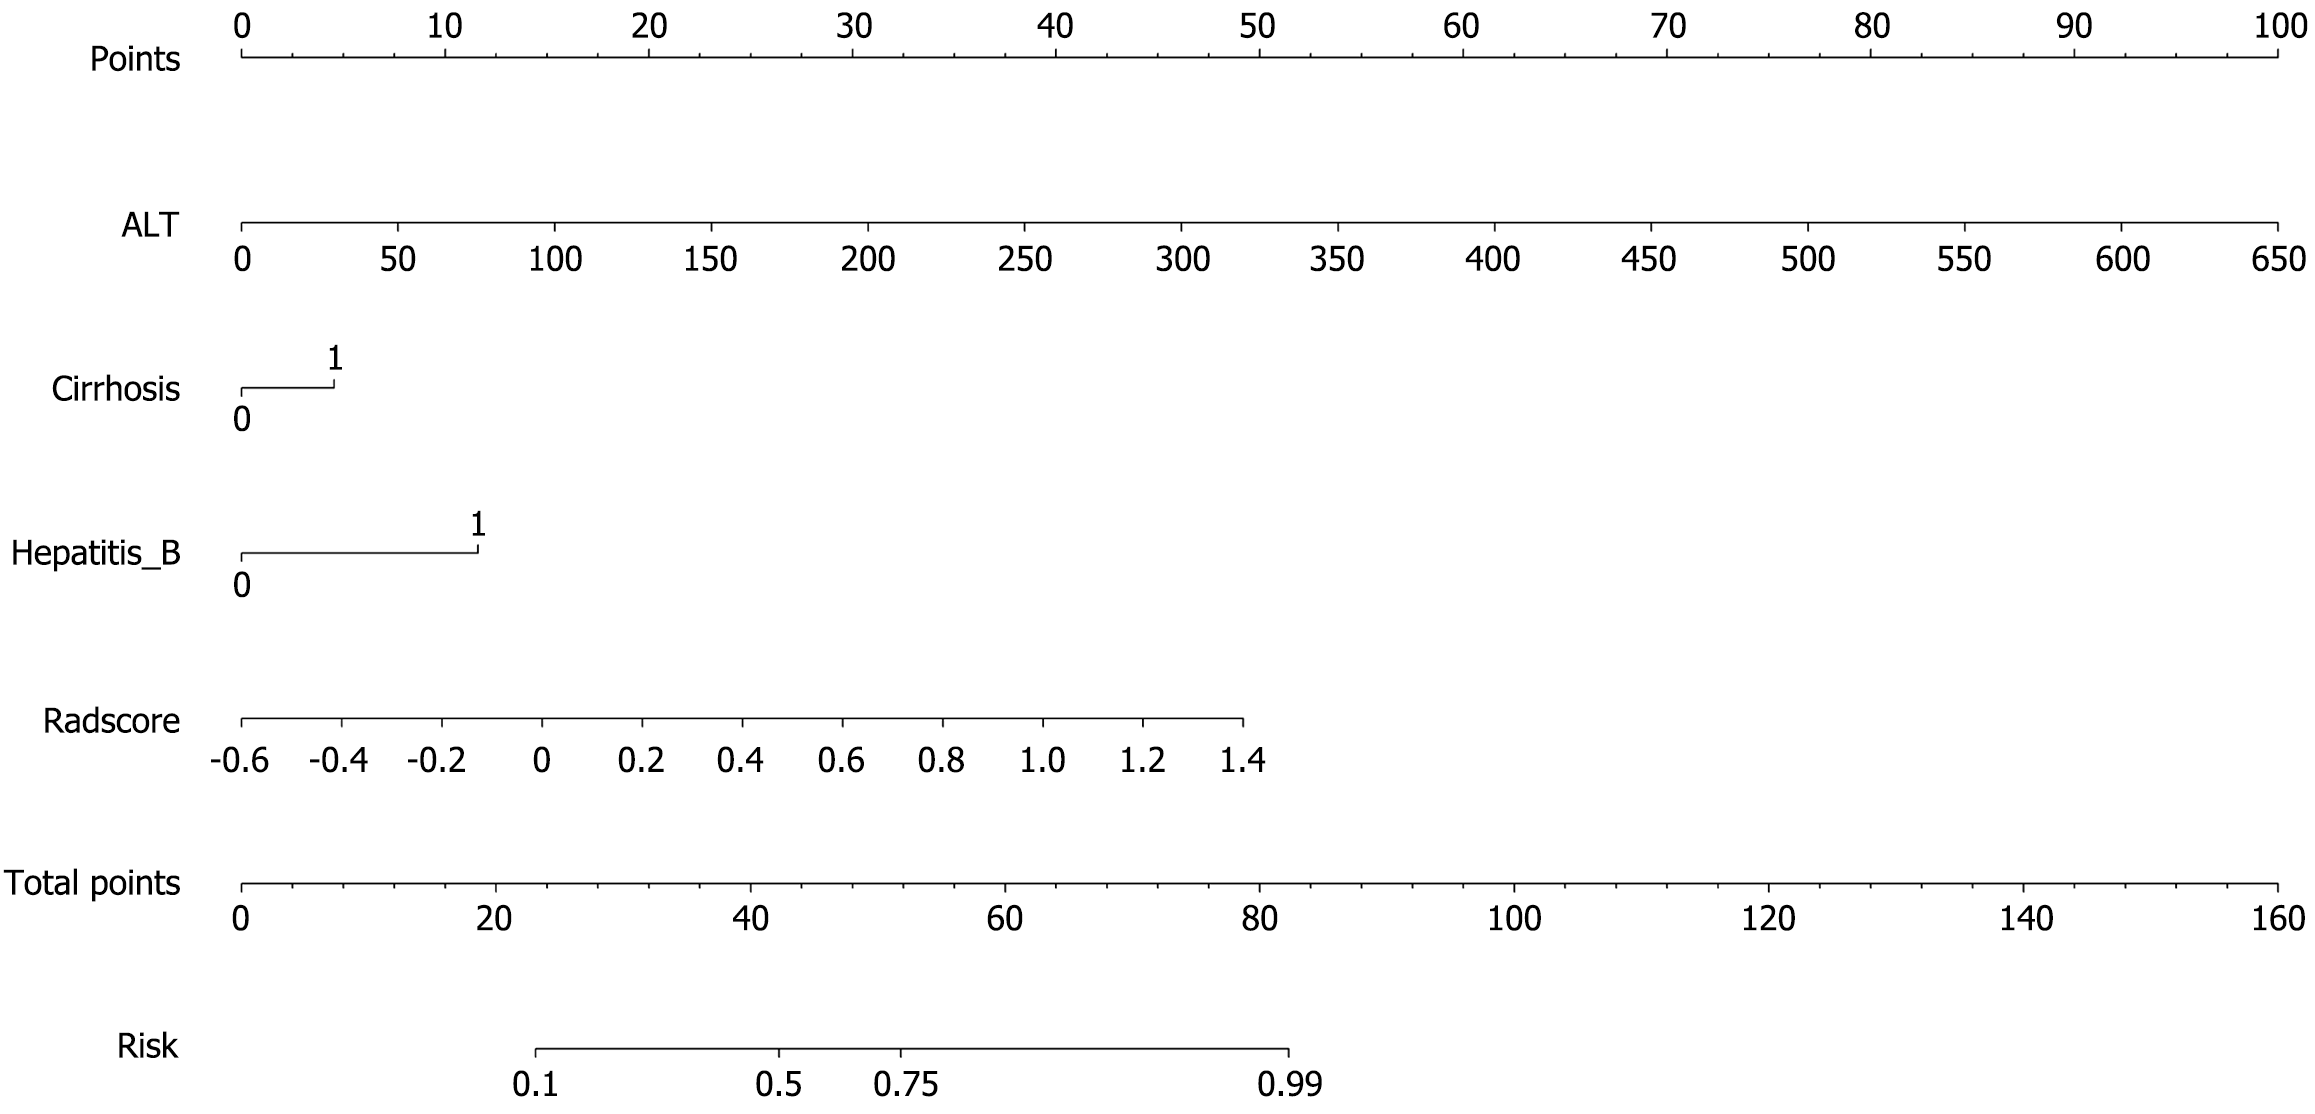

The associations among the clinical features of patients in the training group, the Radscore of the fusion model, and high Ki-67 expression were reported via both univariate and multivariate logistic regression analyses. The computation formula for the Radscore is provided in Supplementary material. The results revealed that Radscore [12.828 (2.467, 66.686), P = 0.011]; alanine aminotransferase (ALT) [1.050 (1.010-1.092), P = 0.040]; hepatitis B virus infection [8.294 (2.651-25.946), P = 0.002]; and cirrhosis [6.698 (2.008-22.354), P = 0.009], showed a positive association with high Ki-67 expression. The specific data are presented in Supplementary Table 3.

A combined clinical-radiomic nomogram was developed by integrating the Radscore from the fusion model with the clinical characteristics from the clinical model. This nomogram achieved an AUC of 0.848 (0.774-0.922) in the training group and 0.830 (0.710-0.951) in the validation group, demonstrating superior predictive performance compared with both the radiomic fusion model and the clinical model alone, as shown in Figures 6 and 7.